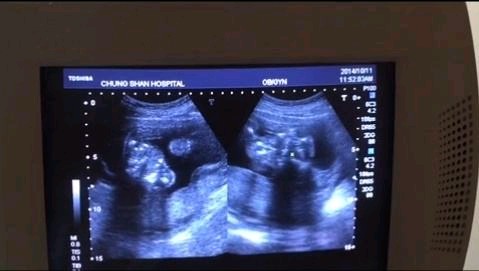

准妈妈们在怀孕期间,免不了都要去做B超。需要检查胎儿在宫内的发育情况了解宝宝的生理情况,但做B超会不会影响胎儿?每个月妈妈心中都是有疑虑的。

总的来说,根据医学具体情况和声波的特殊性,一般情况下,正常妊娠的孕妇整个孕期做4次B超即可。每一次B超检查的时间不要过长,最好不要超过5分钟。不过,如果孕妇发现有阴道出血、突然腹痛以及其他不适,也要随时在妇产科医生的指导下增加b超的检查次数。

第一,一般来说第1次B超检查在怀孕6~7周左右,那排除是不是宫外孕。

第二,第2次B超的话,一般来说到11~13周左右,主要是测量。宝宝头臀长度。来排除胎儿的染色体病变。

第三,第3次B超的话,一般来说在孕中期。也就是22~24周左右,排除胎儿畸形。

第四,第4次B超的话,一般来说可以选择在32~34周左右做,以判断胎位胎儿的大小,以及羊水的多少,有没有脐带绕颈?胎位如何?